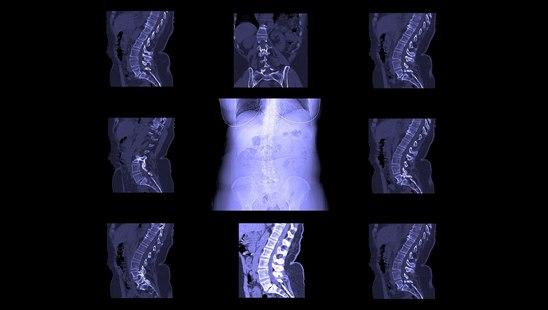

Røntgen av ryggen

Røntgen av ryggen fremstiller de benede delene av ryggsøylen. Mellomvirvelskiver, ryggmargen og nerver er ikke synlige på vanlig røntgen, men avstanden mellom ryggvirvlene viser høyden på mellomvirvelskivene.

Røntgen av ryggen fremstiller de benede delene av ryggsøylen. Mellomvirvelskiver, ryggmargen og nerver er ikke synlige på vanlig røntgen, men avstanden mellom ryggvirvlene viser høyden på mellomvirvelskivene. Ved normal undersøkelse finnes normal skjelettstruktur uten kalkpåleiringer og med normale kurver, normal høyde på mellomvirvelskivene og leddene mellom ryggtaggene på ryggvirvlene.

En lang rekke funn kan gjøres, og det vil føre for langt å gå i detaljer om det. Av hyppige funn som gjøres, er påvisning av redusert høyde på mellomvirvelskiver, slitasje med forkalkninger, beinskjørhet, sammenfall av ryggvirvel, skader eller sykdom på ryggtagger, bruddskader, medfødte misdannelser, tegn til infeksjon, spredning av kreftsykdom til ryggvirvler (metastaser).